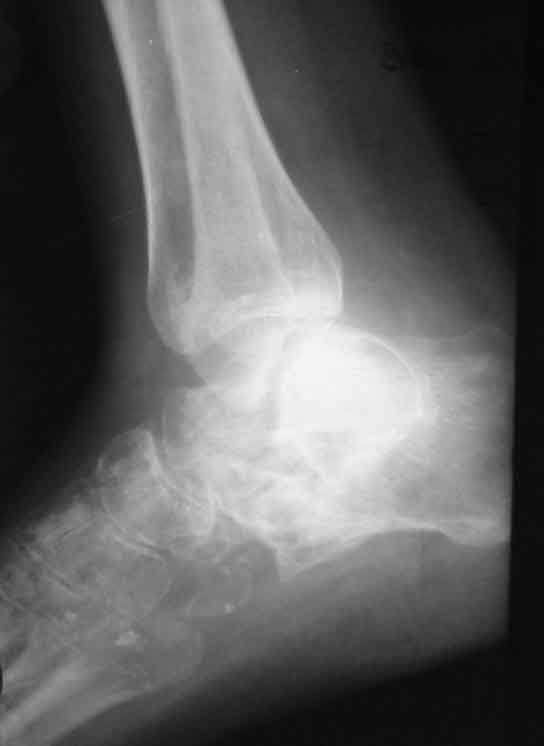

Застарелый вывих пяточной кости

Больная, 41 год, продавец, поступила в плановом порядке. Травма 1 год назад, вышла из двери второго этажа недостроенного дома с высоты 3 м. ДЗ. закр. перелом обеих лодыжек со смещением. Оскольчатый перелом пяточной кости. Вывих пяточной кости в подтаранном суставе кнаружи. При поступлении наложено вытяжение за пяточную кость 27.07 под в/в наркозом попытка устранения вывиха в подтаранном суставе (растягивался голеностопный сустав) безуспешна. Наложен гипс.

В последующем развился некроз кожного лоскута в области внутреней лодыжки 4х5 из-за натяжения кожи над внутренней лодыжкой. Консервативное лечение некроза кожи.Рана в области внутренней лодыжки зажила вторичным натяжением.В настоящее время Больная ходит на костылях с минимальной нагрузкой. При ходьбе беспокоят боли в стопе по подошве, в среднем отделе стопы, в области голеностопного сустава, переднего отдела стопы.Местно: имеется вальгусная деформация заднего отдела стопы, по внутренней поверхности стопы рубец - результат заживления раны вторичным натяжением, при пальпации резкая болезненность по подошвенно-внутренней поверхности стопы, движения в подтаранном суставе отсутствуют, при попытке их совершить появляется боль в проекции подтаранного сустава, сгибание разгибание в голеностопном суставе сохранены, болезненность появляется в крайних положениях сгибания-разгибания, имеются пронационные супинационные движения в голеностопном суставе.ДЗ Сросшийся со смещением перелом обеих лодыжек, подвывих книзу, сросшийся со смещением перелом пяточной кости вывих пяточной кости кнаружи.Коллеги, поделитесь мнением, что делать в такой ситуации?Снимок 1

Снимок 3